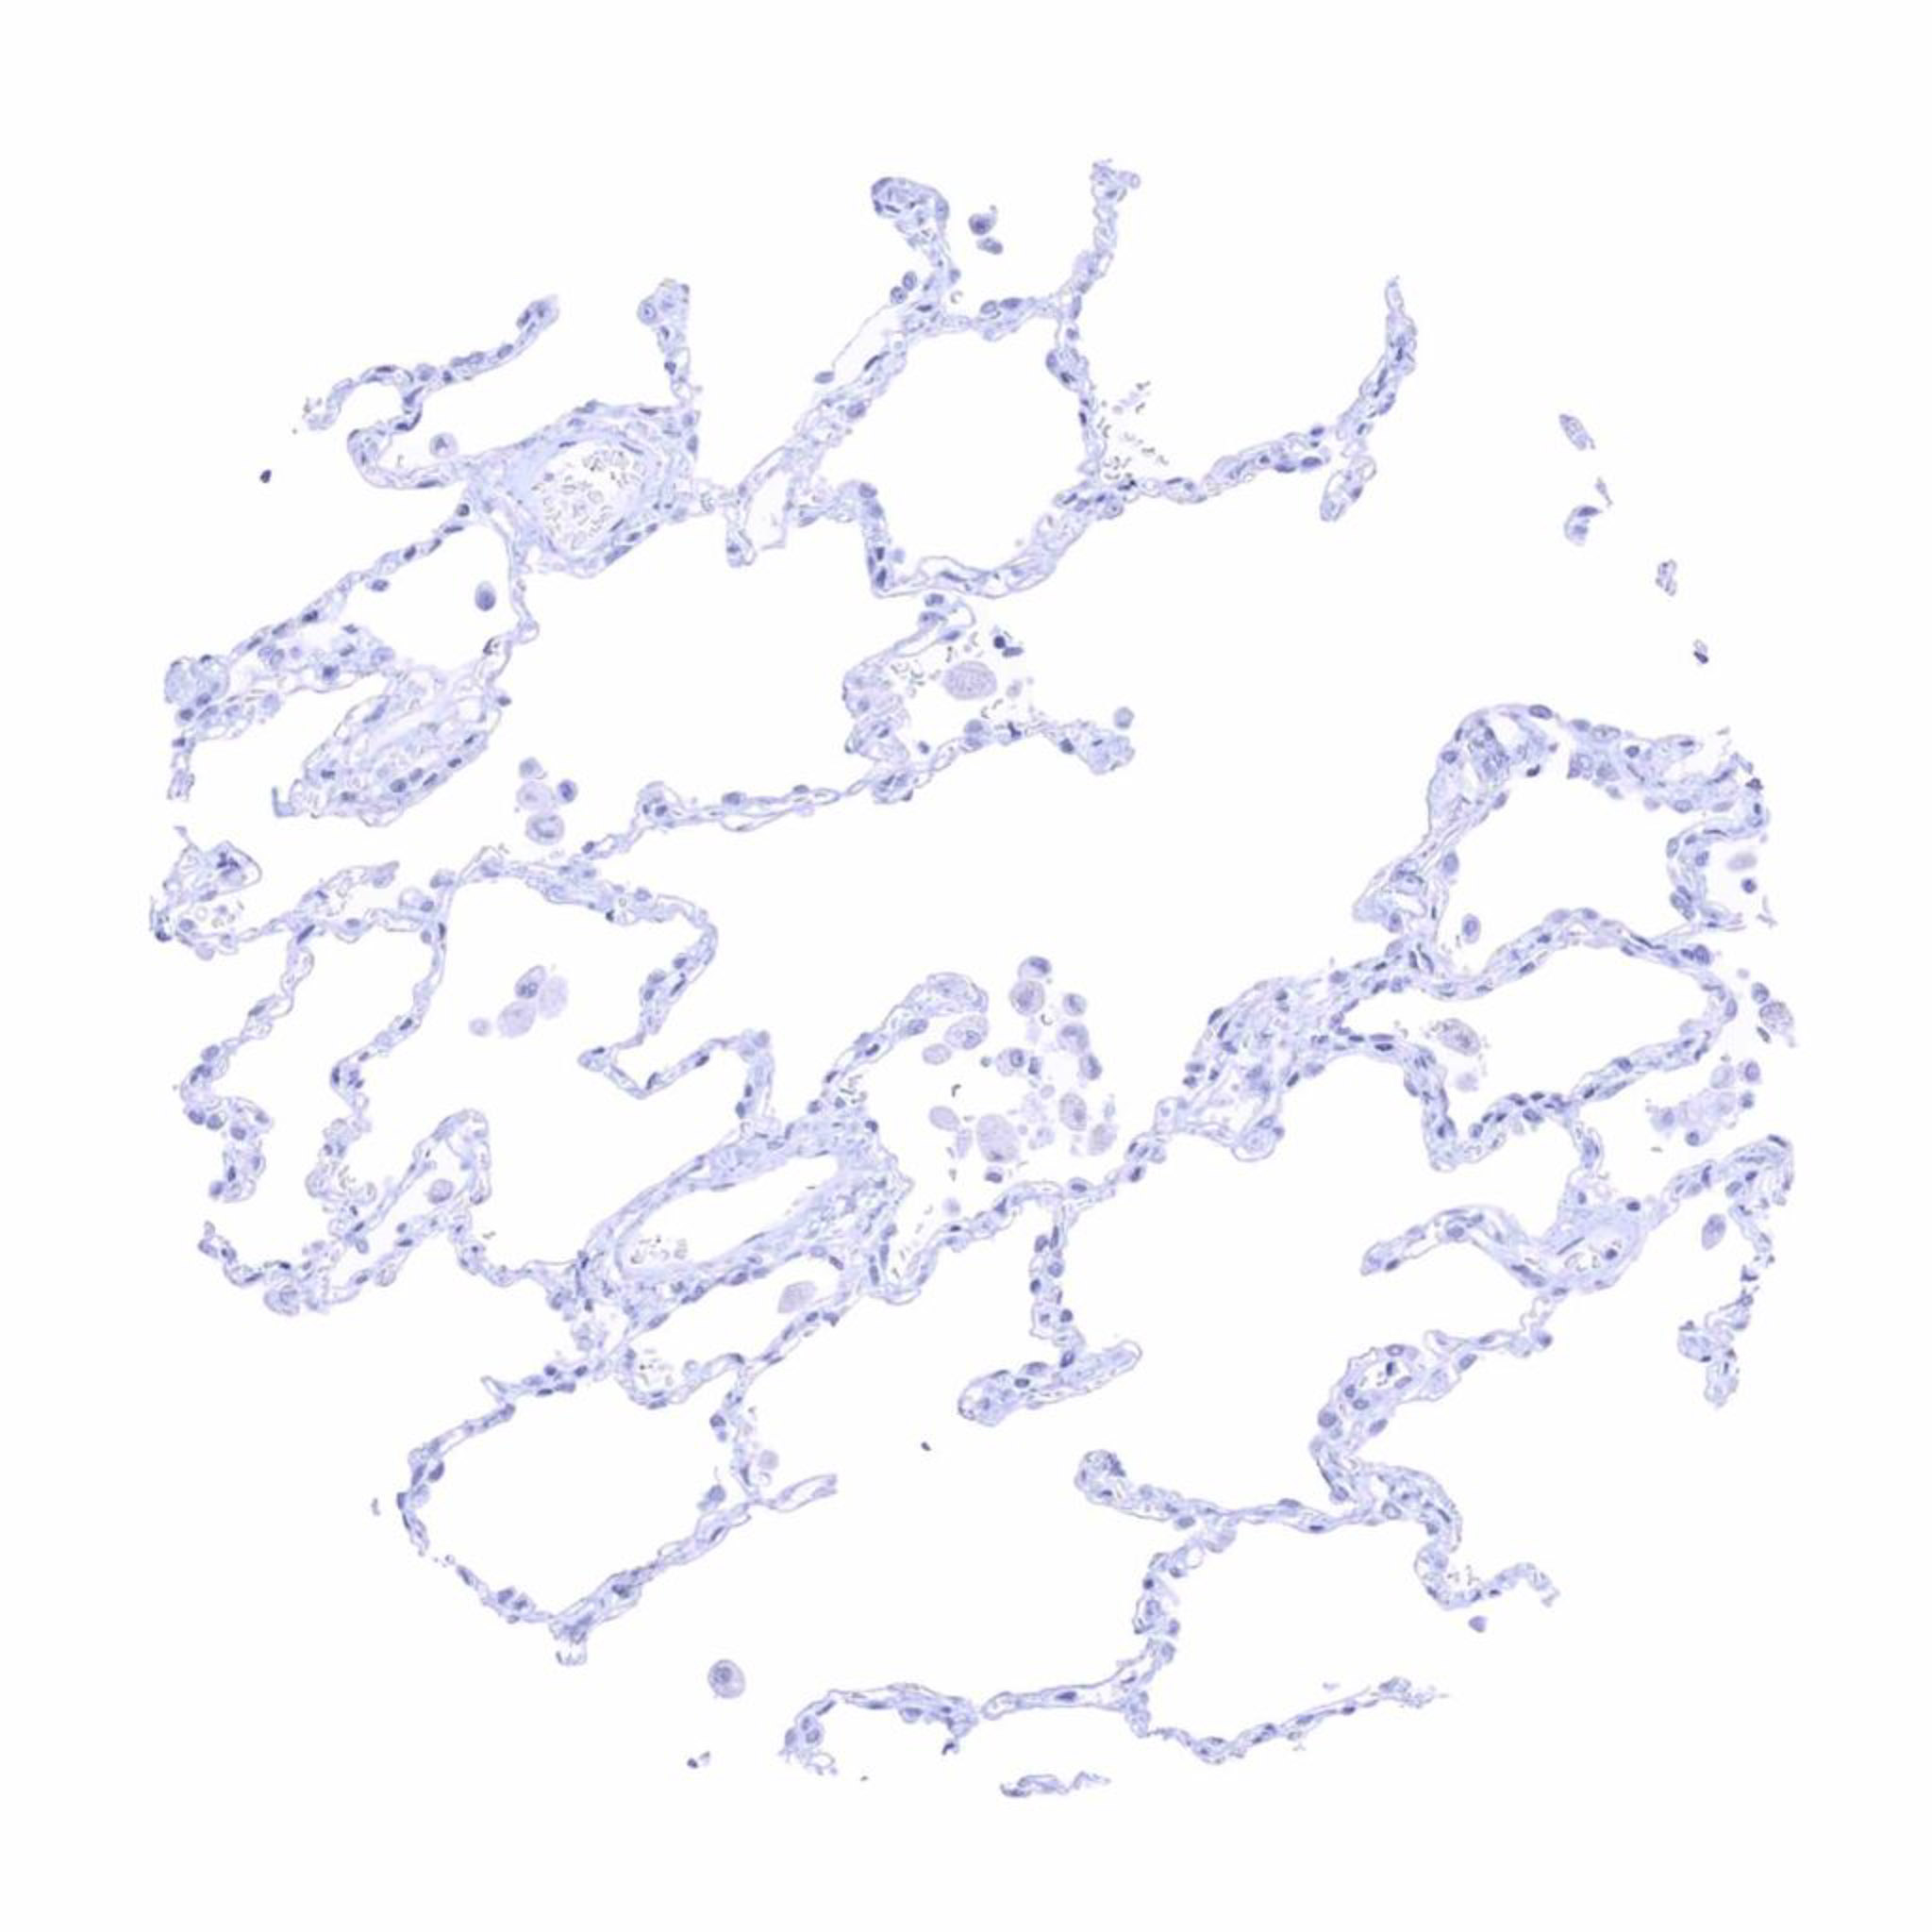

Lung